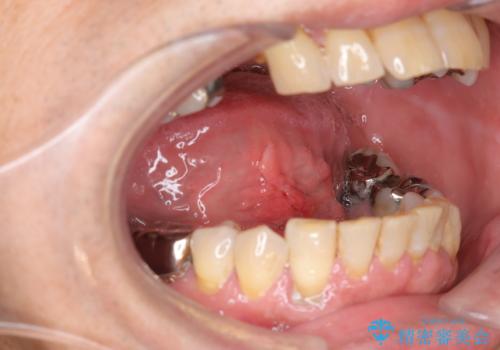

『舌小帯形成術』 ベロの動きを良くして滑舌を改善したい

- 舌の動きが制限され、滑舌を改善したい、と希望され来院されました。

舌小帯形成術を行うことで、滑舌の改善を図ります。形成術は約5分程度で終了し、1週間後に抜糸を行い治療は終了となります。

術後、舌の動きが改善され滑舌の改善を実感することができました。